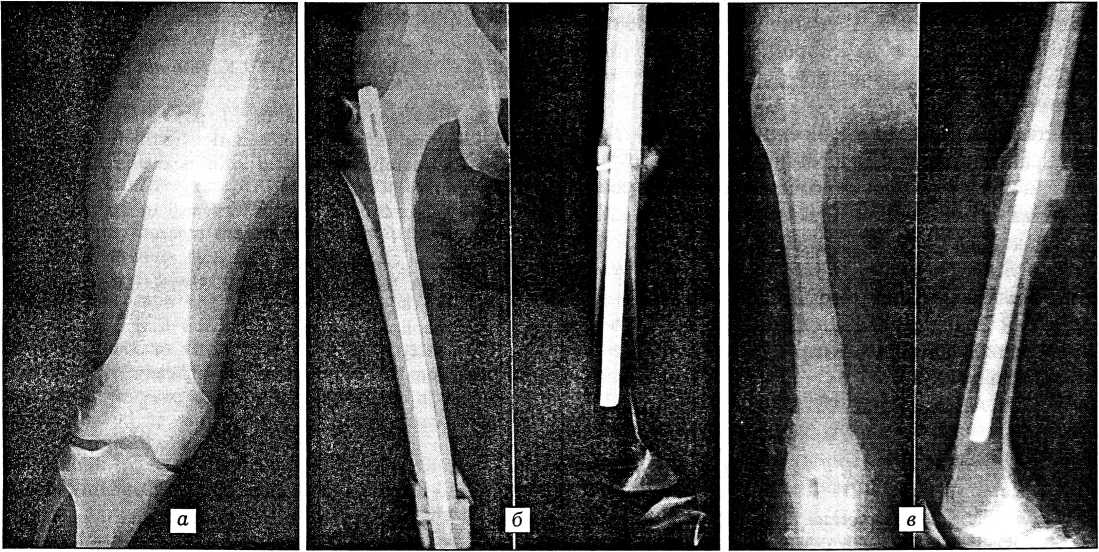

Больной М., 23 лет, поступил в реанимационное отделение института 19.10.97 в 11.05, через час после автоаварии. При поступлении общее состояние очень тяжелое: в контакт не вступает, периодически возбуждается, частота дыхания 22 в минуту, пульс на периферических артериях не определяется, частота сердечных сокращений 120 в минуту, АД 40/0 мм рт. ст. Тяжесть ЧМТ по шкале Глазго 6 баллов. Левое бедро деформировано в средней трети, определяется патологическая подвижность отломков. На краниограммах — перелом свода и основания черепа, на рентгенограммах бедра — оскольчатый перелом в средней трети со смещением отломков (рис. 3, а).

Рис. 3. Рентгенограммы бедра больного М. а — оскольчатый перелом диафиза со смещением отломков; б — после остеосинтеза штифтом и шурупом; в — через 10 мес после операции: перелом сросся

Через 6 ч 45 мин после поступления пострадавшего по витальным показаниям произведена под наркозом операция: краниотомия слева, удаление эпидуральной (100 мл) и субдуральной (5 мл) гематом (рис. 4, б). Послеоперационное течение гладкое. На 2-е сутки после травмы сознание восстановилось до уровня сопора. Гемодинамика стабилизировалась, тяжесть ЧМТ по шкале Глазго — 7 баллов. Под наркозом произведен интрамедуллярный остеосинтез бедренной кости массивным металлическим штифтом и шурупом (рис. 3, б). Операция длилась 50 мин и прошла без осложнений. Послеоперационные раны зажили первичным натяжением.

объеме движений в суставах оперированной конечности. Опороспособность и функция поврежденной конечности восстановились через 4 мес после операции. Перелом сросся (рис. 3, в).